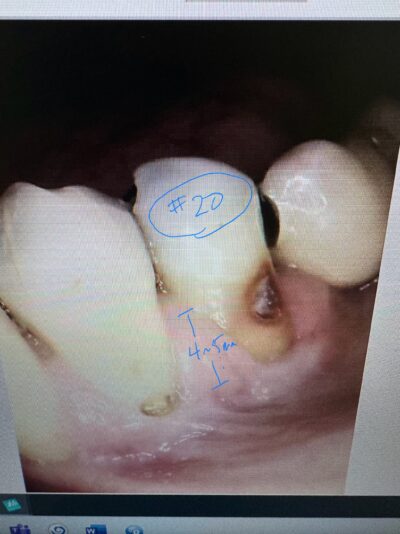

Dr. started the discussion #20 implant in the forum Complications a year ago

Hi, this implant was placed in June 2024. I have 3PAs (one from day of placement, one month later, and 9 month later). The intraoral picture of the soft tissue is from yesterday and tissue looks great… patient has no discomfort/pain either. She did have some discomfort between 2-3rd week after placement but subsided after taking…